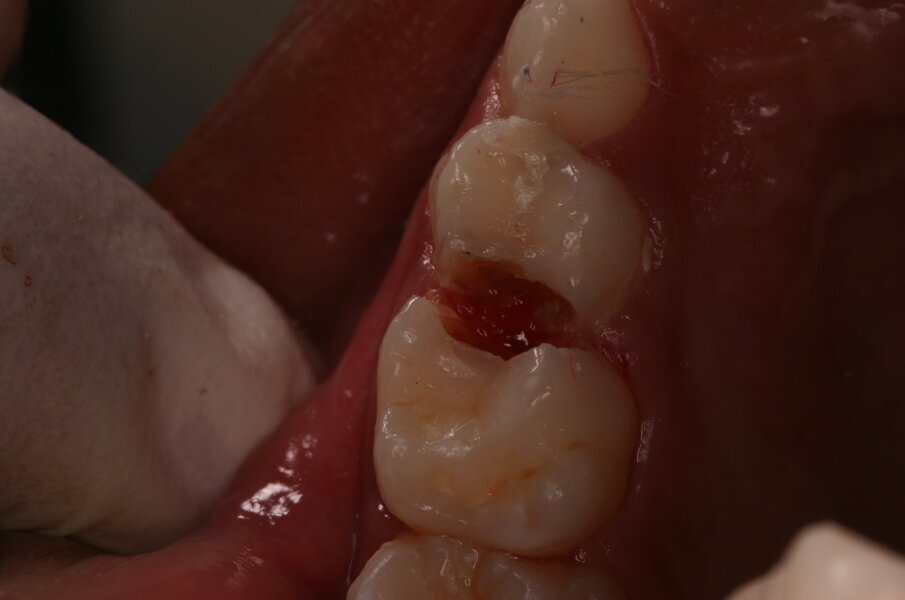

Afbeelding 5a. Onvoldoende toegankelijke caviteit mesiaal in de 65, distaal in de 64 en mesiaal in de 64.

Afbeelding 5b. De gedemineraliseerde caviteitsranden zijn onondersteund en fractureren gemakkelijk door met een glazuurmes erop te drukken.

Afbeelding 5c. De kleine mesiale caviteit in de 64 is door middel van de ART-methode gerestaureerd. De andere twee caviteiten zijn nu toegankelijk voor tandenborstel en fluoridetandpasta.